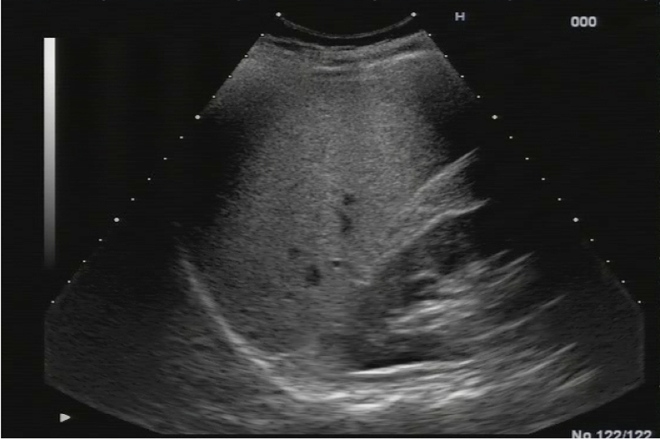

Características físicas del hígado